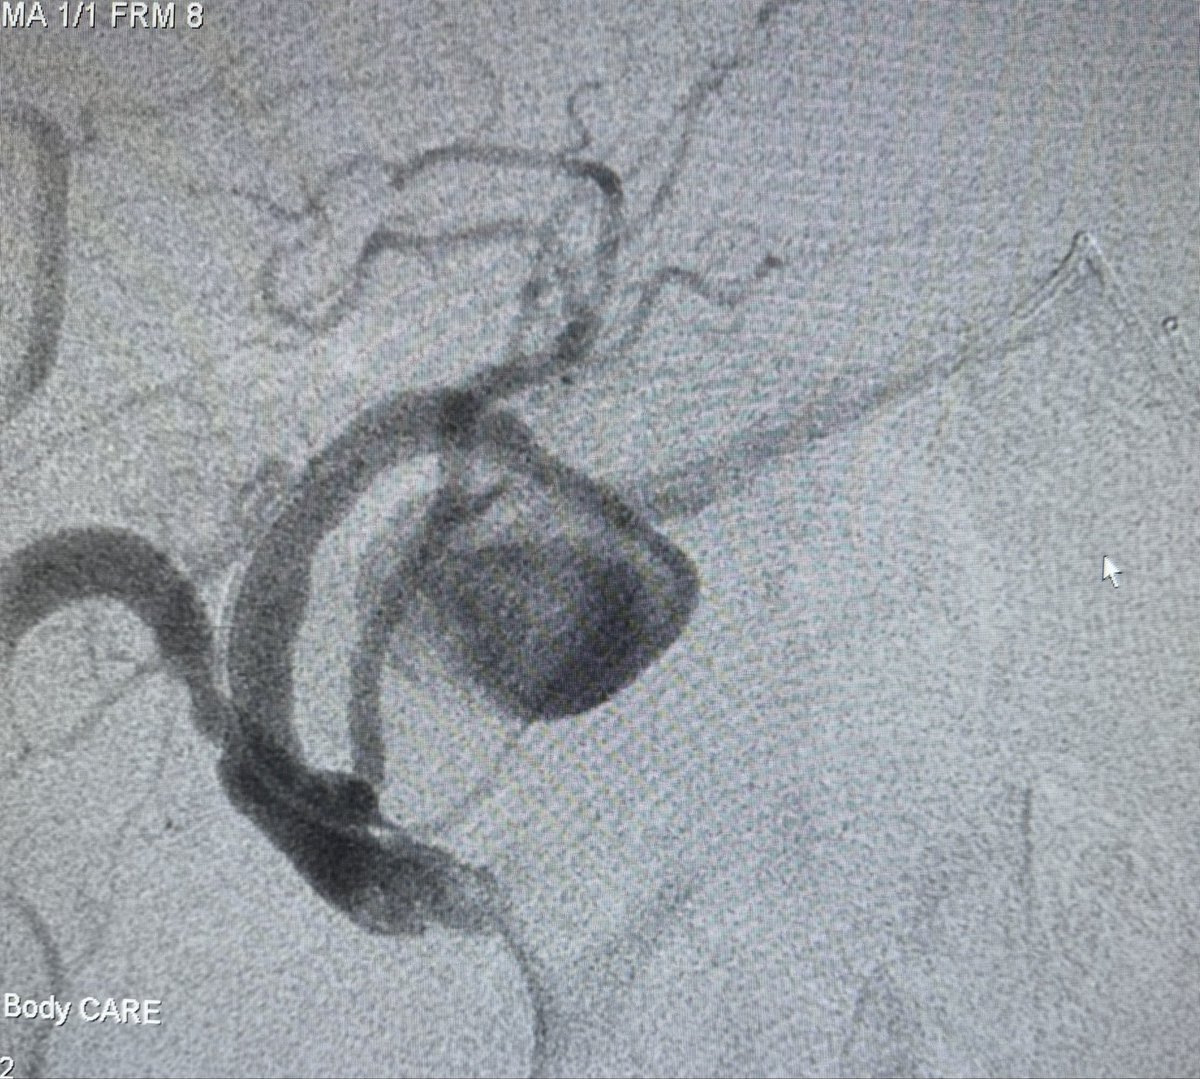

80 hrs of call #rupture #aorta #EVAR x2 #Endoanchors @MDT_Cardiac #DVT @Pen #GSW fem artery